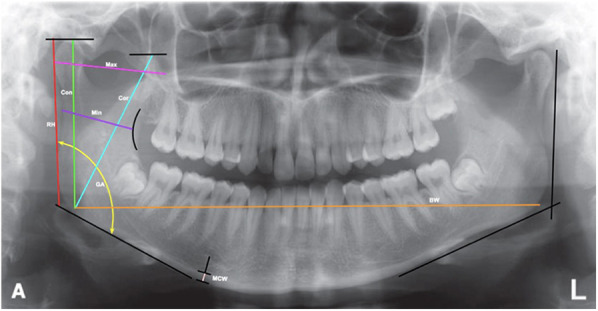

Methods: A total of 300 panoramic radiographs were analyzed. Mandibular morphometric parameters were measured, including ramus height, maximum and minimum ramus width, gonial angle, bigonial width, condylar height, coronoid height, MCW, and MCI. Statistical analysis included Spearman's correlation, multiple regression, and logistic regression to assess the relationships between mandibular morphology, cortical width, and cortical erosion with age and sex.